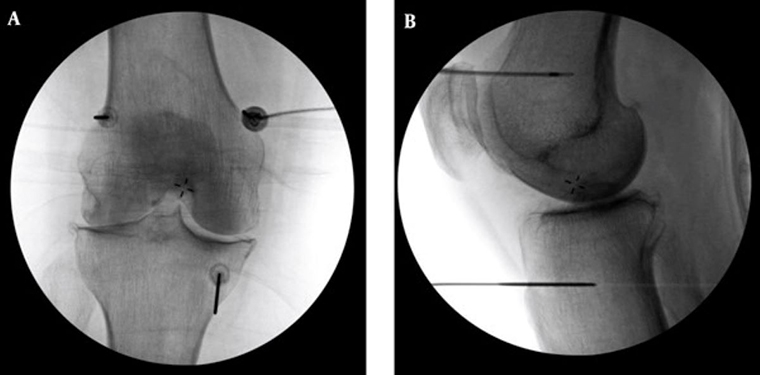

李宜軒醫師表示,高頻熱凝療法過往多用於椎間盤突出、滑脫等脊椎神經壓迫造成的下背痛、坐骨神經痛的止痛治療,近來也運用至膝關節退化。執行方式是在局部麻醉的情況下,以X光定位將電極導針導引至膝蓋的三個主要感覺神經叢,確認施行目標後,接上電源線輸出高頻電波,藉由熱能與電效應,使引起疼痛的神經失去傳導疼痛的能力,降低疼痛。

# 首圖來源/台北慈濟醫院提供